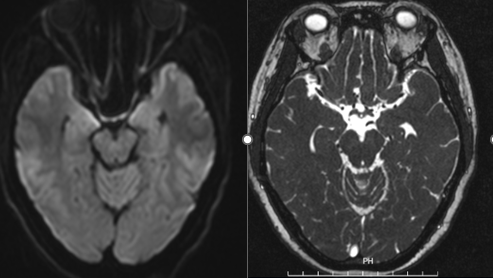

Trước tình trạng trên người bệnh được hướng tới chẩn đoán tổn thương dây thần kinh số IV trung ương, được chỉ định chụp CHT sọ não, CHT cột sống cổ, xét nghiệm dịch não tủy, xét nghiệm bilan viêm, tự miễn, nhiễm trùng trong máu, xét nghiệm tự kháng thể Oligoclonand band; Aqb4. Hội chẩn chuyên khoa mắt, soi tai mũi họng để sàng lọc u vòm…

Hình ảnh kết quả chụp cộng hưởng từ của người bệnh

Dựa trên các kết quả dịch não tủy, máu, CHT sọ não, CHT cổ, kết quả tự kháng thể… các bác sĩ đã hội chẩn và đưa ra chẩn đoán Liệt dây IV trung ương căn nguyên do viêm và đã áp dụng phác đồ: corticoid liều cao, vitamin nhóm B, tăng dẫn truyền thần kinh, dinh dưỡng thần kinh. Sau 2 tuần điều trị vận động nhãn cầu về các phía đã đạt tối đa như mắt trái, khám vận động 2 mắt cân xứng, người bệnh hết các triệu chứng nhìn đôi, tự tin bỏ che mắt khi đi lại, lên xuống cầu thang bình thường, không còn cảnh nhìn món này lại gắp phải món khác. Người bệnh được ra viện dùng thuốc theo đơn ngoại trú trong niềm hạnh phúc của gia đình.